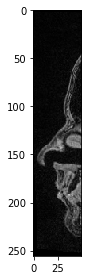

De même, nous pouvons sélectionner tous les pixels jusqu’à une position donnée.

sub_region_x2 = image[:, :, :50]

imshow(sub_region_x2[100])

../_images/b1b6f01794a399ac2db4297973bb8e34233be52f6b5d98b70d683d3a5cd5f8df.png